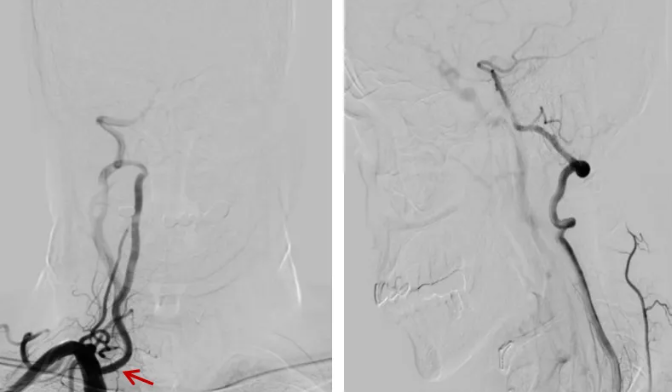

支架植入:沿导丝送入椎动脉药物支架至狭窄段,采用「半释放」技术,在导引导管辅助下逐步打开支架,确保位置精准。

术后造影:支架完全膨开,支架位置满意,前向血流改善。